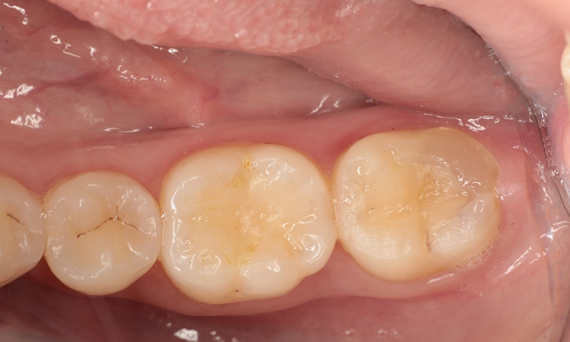

Before: Pre-operative clinical scenario after endodontic therapy.

After: 1 month after the CEREC Tessera onlay was bonded.

Second lower right molar in 90 minutes

A CEREC Tessera onlay

A 20-year-old female patient had endodontic treatment of her lower right 2nd molar. A chairside onlay was fabricated from the new high-strength ceramic CEREC Tessera ALD.

Dr. Aniruddha Nene

Pune, India